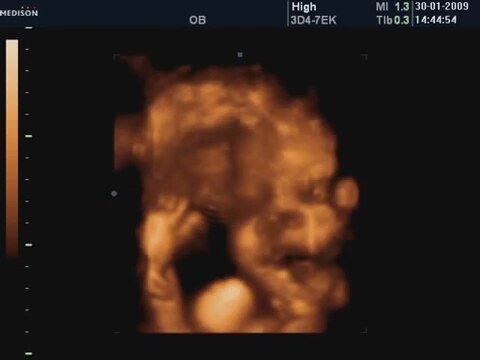

34 Haftalık Bebeğin 4 Boyutlu Ultrason Görüntüsü